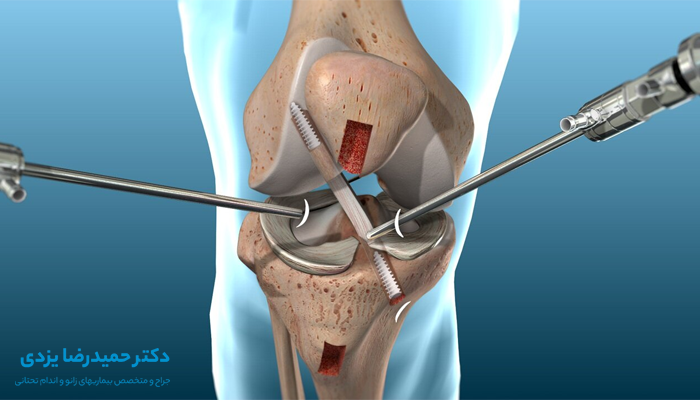

آسیبدیدگی رباط صلیبی قدامی (ACL)

آسیب رباط صلیبی قدامی (ACL) یکی از شایع ترین آسیب های ورزشی زانو در ورزشکاران بوده که در اثر توقفهای ناگهانی، تغییر مسیرهای سریع، یا فرودهای نادرست در ورزشهایی مانند فوتبال، بسکتبال و اسکی دانهیل ایجاد میشود.

این نوع آسیب با علائمی نظیر صدای ترکیدن زانو، درد شدید، تورم فوری و احساس عدم پایداری همراه است. بروز چنین شرایطی ورزشکار را از ادامه فعالیت بازنگه میدارد و در صورت عدم درمان مناسب، مشکلات جدیتری نظیر آرتروز زانو را به دنبال خواهد داشت.

درمان آسیب ACL بسته به شدت آن، از استراحت و تمرینات توانبخشی تا جراحی ACL و بازتوانی متغیر است. البته استفاده از برنامههای تمرینی پیشگیرانه، خطر بروز این آسیب را به میزان قابلتوجهی کاهش میدهد.